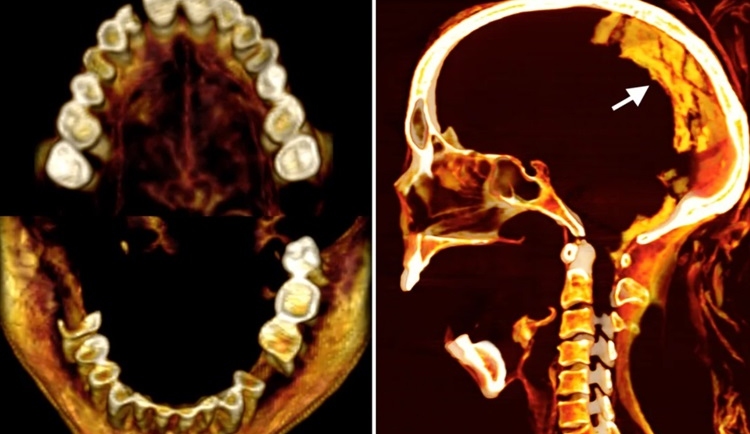

Xác ướp của người phụ nữ Ai Cập cổ đại vẫn giữ nguyên biểu cảm la hét vì đau đớn khi chết sau 3.500 năm.